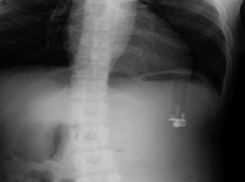

В мире Газовую зажигалку обнаружили врачи в желудке американца

02.11.2017

Зажигалка спровоцировала образование язвы желудка